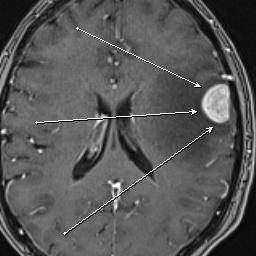

Пациентка М. поступила в нейрохирургическое отделение с жалобами на сильную головную боль и слабость в правых конечностях. Была произведена РКТ головного мозга, где была выявлена опухоль левой лобной доли. Для уточнения диагноза в ГАУЗ РТ БСМП была произведена МР-томография с МР-спектроскопией. Были получены данные о метаболическом составе очага, что точно соответствовало метастатическому поражению. При последующем онкопоиске первичного очага был выявлен Са правой молочной железы и метастазы в позвонке.